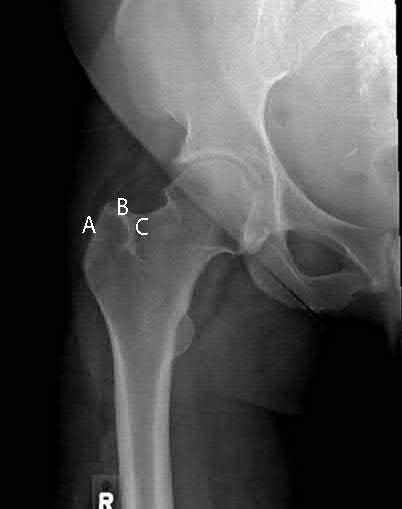

When using a trochanteric femoral nail, placing your start point in which area will result in varus deformity?

1) A

2) B

3) C

4) A and B

5) B and C

Placing your start point lateral to the tip of the greater trochanter (location A) will cause varus deformity.

When using a trochanteric entry femoral nail, the ideal starting point is just medial to the tip of the greater trochanter. Placement lateral to the tip of the trochanter will cause varus malalignment.

Ostrum et al. in a cadaveric study, reported on deformities following medial, standard, and lateral starting points for trochanteric entry femoral nails. Nails inserted too medially yielded excessive valgus, while nails inserted too laterally yielded varus malalignment. Those started at the tip yielded the most neutral alignment, but still with slight varus. The authors recommended a start point just medial to the tip of the greater trochanter.

Figure A exhibits ideal starting point for a trochanteric entry nail (B), for a piriformis start nail (C) and a start point that is too lateral, causing varus (A). Illustration A depicts 4 different types of trochanteric entry nails that started at the tip of the greater trochanter and although mostly neutral, still exhibit slight varus.